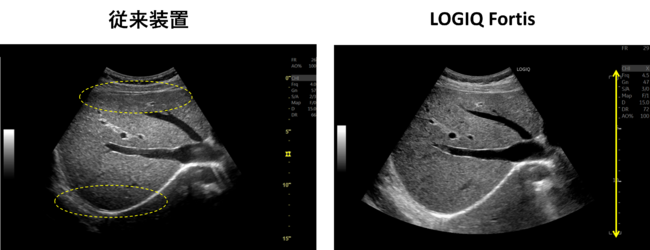

従来装置ではフォーカス近傍が明瞭に描出されているが,フォーカス以外の部分は明瞭に描出できておらず,関心領域に応じてフォーカスの位置を適宜変更する必要がある。LOGIQ Fortisでは,フルフォーカスにより浅部も深部も明瞭に描出され,フレームレートも高い。